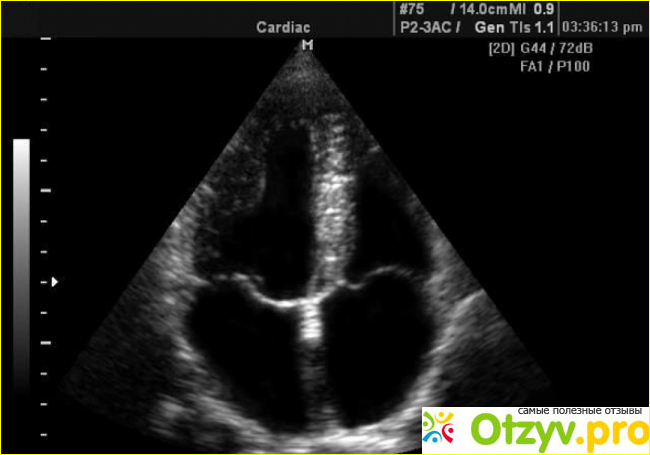

Эхокардиограмма сердца

УЗИ сердца или ультразвуковое исследование сердца ещё называют эхокардиограммой. Она является безопасным и достаточно современной методикой обследования, и здесь практически отсутствуют какие-либо противопоказания. Проведение данной процедуры является обязательным для лиц, которые профессионально занимаются спортом, а также тех лиц, которые имеют дело с высокими физическими нагрузками.

Как ни странно, некоторые люди почему-то боятся проводить данную процедуру и связано это прежде всего со страхом ее неприятности и болезненности. Однако следует помнить, что проведение эхокардиограммы является полностью безболезненным, и мало положительным по времени. Всего процедура занимает от 15 до 20 минут. Всё проводятся в лежачем положении на спине, нужно будет только снять всю одежду до пояса и разные украшения, в частности серьги и кольца. Для проведения процедуры применяется совершенная ультразвуковая аппаратура. Обследуемуму на тело и на грудь ставятся в специальные датчики, благодаря которым можно получить данные сердца, сосудов и как проходит кровоток. Чтобы происходила передача импульсов применяется специальное гелеобразное вещество, которое наносят на грудную клетку пациенту. Что касается ощущений, то они ничем не отличаются от таковых, когда проводятся обычное стандартное ультразвуковое исследование, в частности, например, при беременности.

Чаще всего проводят стандартную эхокардиограмму, однако есть еще и другие методы исследования - это стресс-эхокардиограмма и чреспищеводная кардиограмма. Для проведения данной процедуры необходимы соответствующие знания, и обычно проводится она соответствующими специалистами в хороших клиниках.